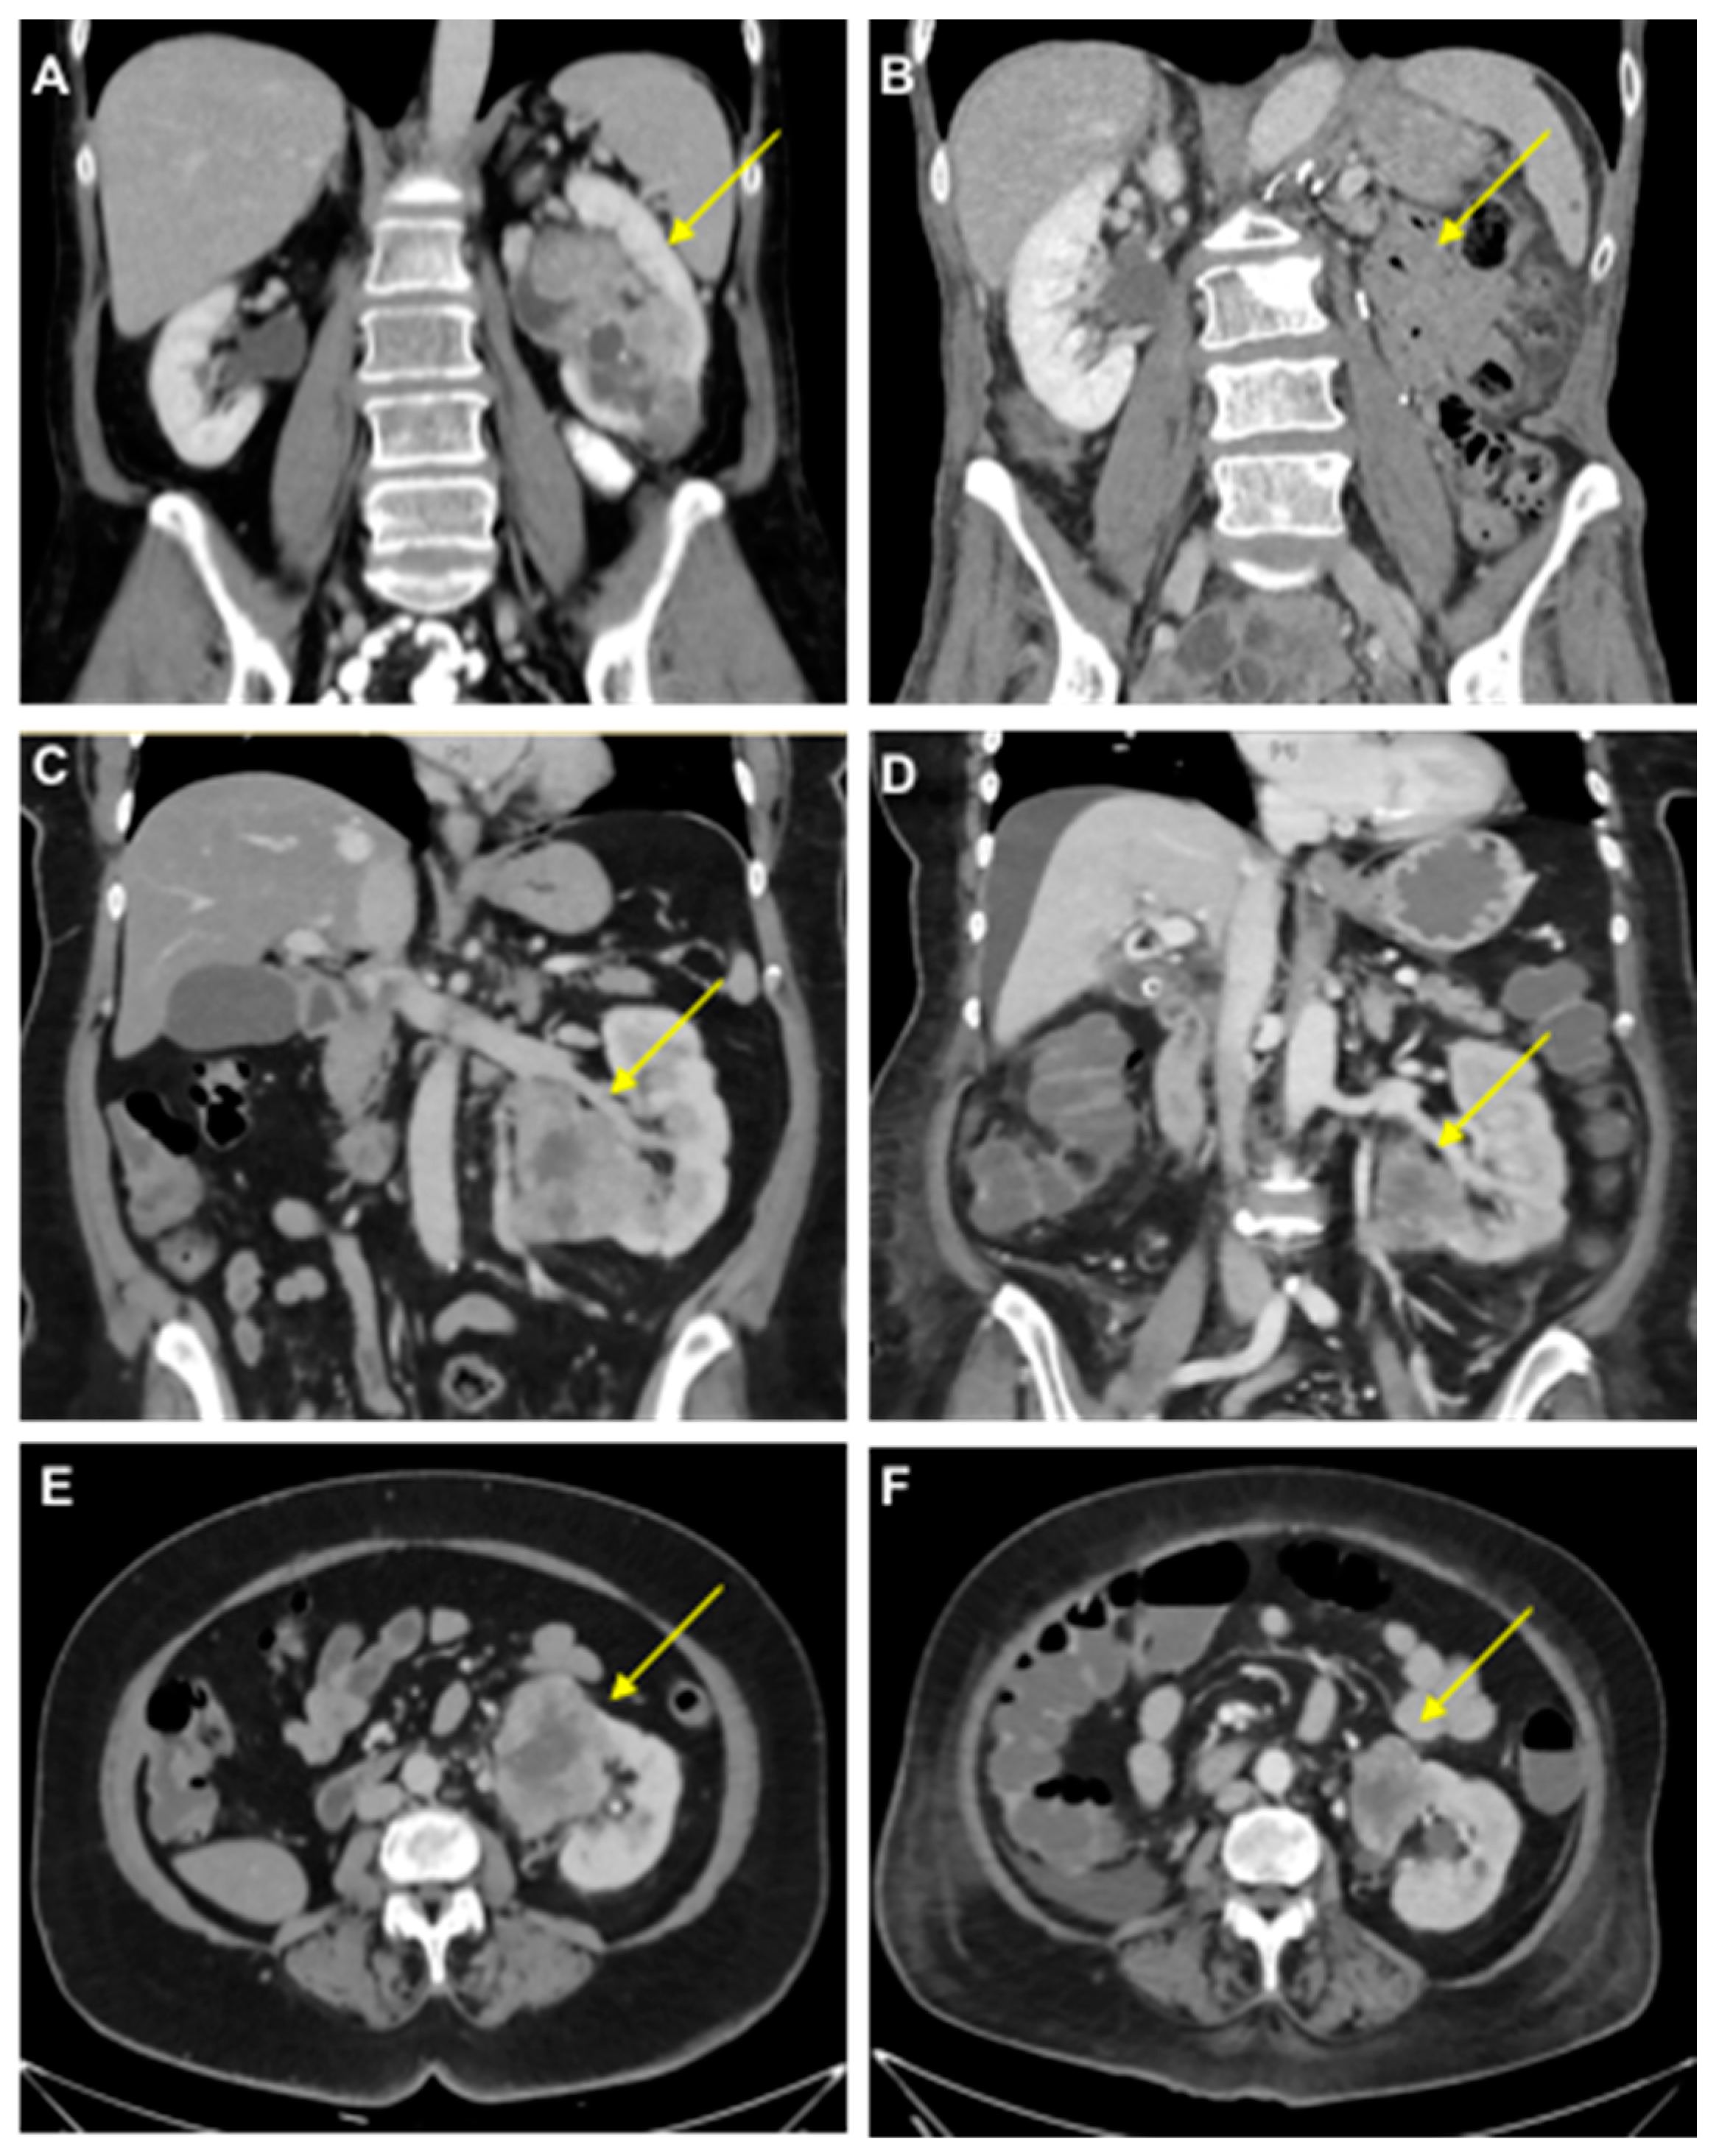

We performed a urine PD-L1 analysis before and after cytoreductive tumor nephrectomy before the start of radiotherapy (Figure 1). The PD-L1 level decreased from 117 pg/mL before therapy to 25 pg/mL (4.7-fold reduction) in this patient (Figure 2).

Figure 1.

Clinical course of mRCC patients. (A,B) Computed tomography scans of the primary tumor in a 58-year-old female with oligometastatic mRCC before (A) and after (B) a left-sided tumor nephrectomy (Patient 1). (C–F) Tumor-bearing left single kidney in a 63-year-old female patient with congenital renal agenesia on the right side before (C,E) and after (D,F) the first cycle of therapy with ipilimumab/nivolumab with tumor regression (−31% after RECIST; Patient 2). Arrows indicate RCCs except in B.

A 63-year-old woman (Patient 2) presented with metastatic clear cell RCC, initially diagnosed after the resection of a frontal skull metastasis. Staging revealed a large renal tumor of the left kidney with metastatic lesions in the bones, lungs, brain, adrenal gland, lymph nodes and skull. The patient had a single kidney due to congenital renal agenesia of the right side. After resection of the skull metastasis, systemic therapy with ipilimumab and nivolumab was initiated, accompanied by local radiotherapy. The panel NGS of the primary tumor revealed pathogenic mutations in VHL, BAP1 and NF2 and likely pathogenic mutations in KDM6A, as well as ABL. After the first cycle of immunotherapy, the patient showed radiographic tumor regression (−31% after RECIST; Figure 1). The patient deceased due to complications of severe candida sepsis before the second cycle could be administered. The urine of this patient was collected and analyzed for PD-L1 before and after immunotherapy. Three weeks after the first dose of the first cycle, the urine PD-L1 level had decreased from 164 pg/mL before therapy to 12 pg/mL (13.7-fold reduction; Figure 2).